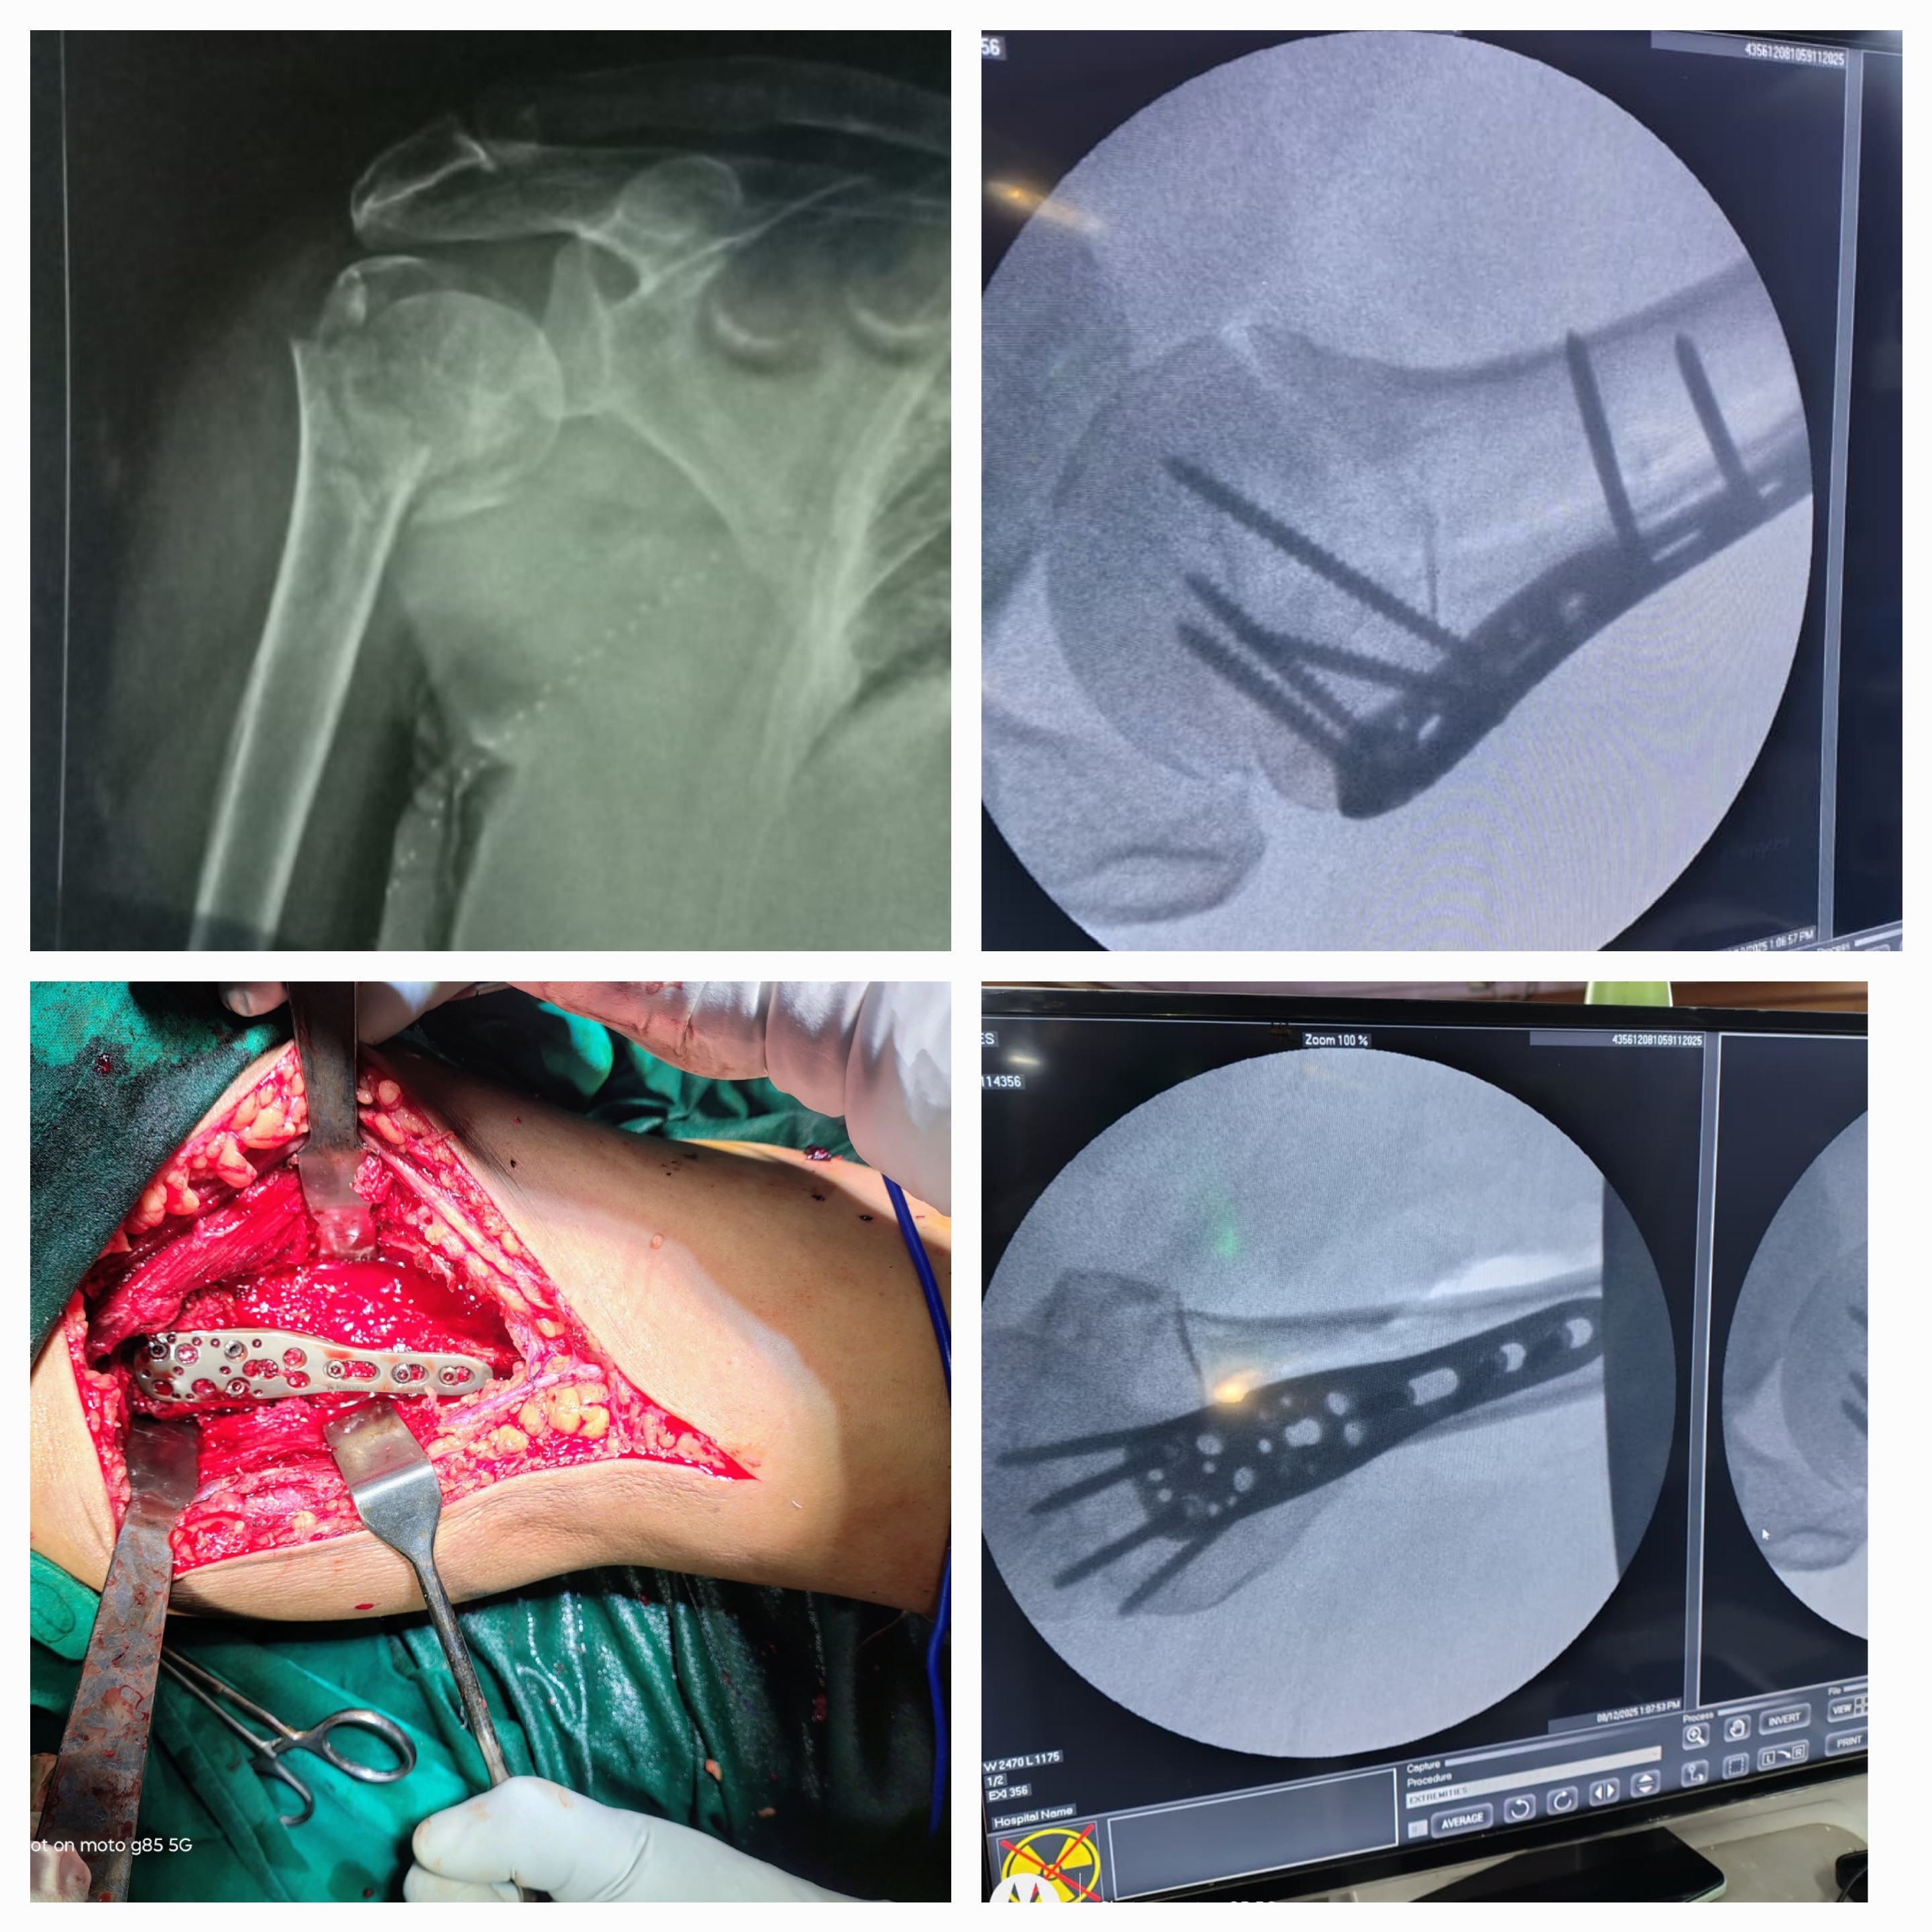

Sunshine Ortho Pain Superspeciality Hospital is the Best Multispeciality Hospital, Orthopedic Hospital in Wakad, Hnjewadi, PCMC and Pune. We are specialized in Orthopedic Surgeries, Robotic Joint Replacement Surgery, Hip and Knee Replacement Surgery, Complex Trauma And Pelvi Acetabular Surgery, Spine Surgery, Sports Medicine And Arthroscopy, Regenerative Therapy/Prolotherapy, Shoulder Surgery, Knee Surgeries, Foot And Ankle Treatment in Wakad, Hinjewadi, PCMC and Pune.